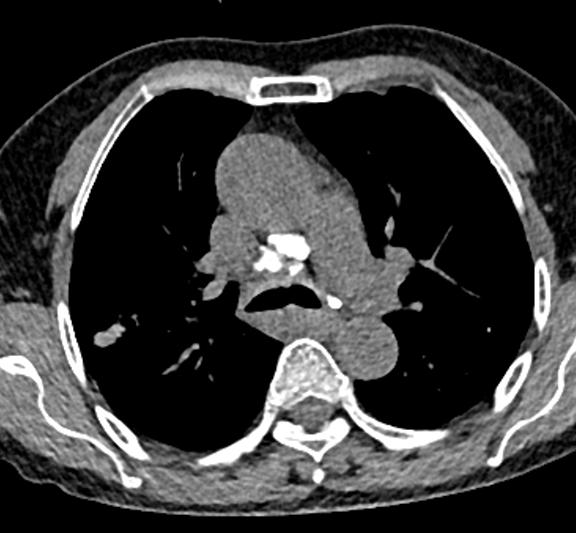

图10~图15 胸部CT示双肺多发钙化灶

问题出在哪儿?

右中间支气管的钙化病灶向外移动,钙化病灶的尖端刺激到支气管粘膜了(图16)。

图16 胸部CT